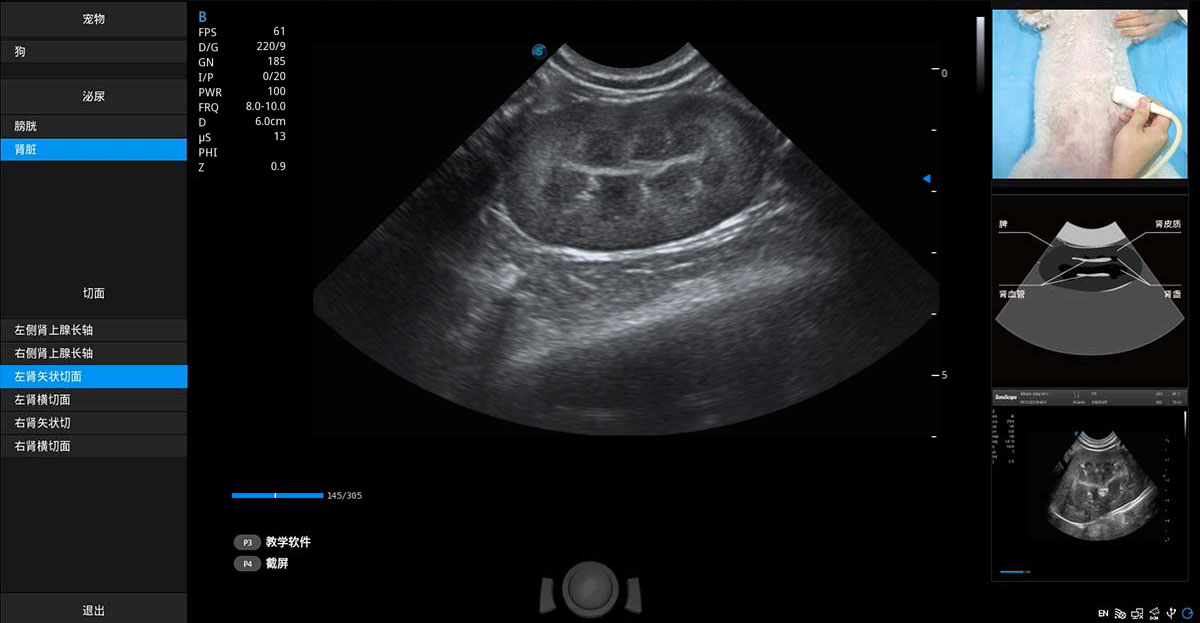

ProPet 80 专为动物医生设计,对不同的动物体型和生理结构作出了针对性的优化。通过动物影像专用软件,可满足个性化的应用需求,帮助动物医生获得更精确的诊断数据。

提供解剖示意图、标准超声图像、扫查手法涂和操作者实时检查图像,指导操作者进行标准切面的正确扫查。